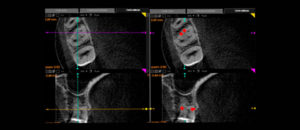

El «Área de contacto» es un término que se usa para denotar las alturas proximales del contorno de las superficies mesial y distal del diente.